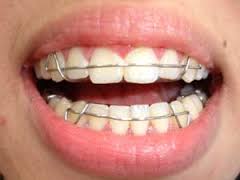

a) fixním aparátem (zámečky, kroužky nalepené na pevno, průběžné drátěné oblouky připevněné gumičkami k aparátu)

Průměrná doba léčby je cca 2 roky, dle závažnosti ortodontické vady. Pravidelné návštěvy po 4-6 týdnech. Při pravidelných kontrolách dochází k výměnám drátěných oblouků a elastických barevných gumiček. Postupně se přechází ze slabých pružných oblouků na silnější rigidní ocelové oblouky. Pacient může cca 2-3 dny po každé výměně oblouku cítit mírné mravenčení, event. táhnutí.

Nutná je dobrá spolupráce pacienta při čištění zubů v okolí fixního aparátu. Na hygienu v průběhu léčby je kladen velký nárok. Každý pacient je důkladně vyškolen ohledně čištění zubů s fixním aparátkem, včetně doporučení potřebných kartáčků.

Jakmile je léčbou dosaženo patřičného výsledku, zuby jsou rovné a správně do sebe zakusují, dochází k sejmutí fixního aparátu. Následuje retenční fáze léčby.